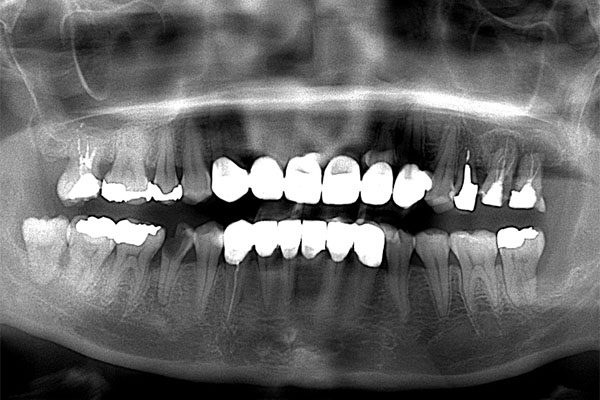

【担当医師所見】

右上の銀歯の下にあった虫歯は大きかったものの歯の神経を残すことがなんとかできたので部分的なセラミックのつめ物(セラミックインレー)での治療となりました。

また反対側の奥歯も古くなっており、将来性を考えセラミックへ変更しています。

右下の大臼歯部は抜歯後治癒を待ち、骨造成とインプラント埋入を同時に行いました。上部構造はFCZ(ジルコニアセラミッククラウン)となっています。

また左下の親知らずは虫歯のため抜歯、左下7番と5番はセラミックインレー、6番はFCZにて補綴しました。

※FCZ:ジルコニアより少しマイルドな硬さで審美性と機能面に優れているクラウン

全体の治療終了より1年半経過していますが、右下インプラント周囲に骨吸収の像など無く問題なく経過しています。またその他虫歯治療部位や歯の神経治療部位に関しても病変の所見は無く概ね良好と思われます。